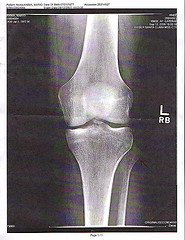

Osteoporoza jest chorobą układu kostnego. Charakteryzuje się zanikiem masy kości i upośledzoną budową tkanki kostnej. Jej najbardziej odczuwalną i niebezpieczną konsekwencją jest zwiększona łamliwość kości i podatność na złamania.

Przyczyny powstawania osteoporozy są bardzo różne. Według lekarzy, najczęstszą przyczyną tej choroby jest podeszły wiek, brak syntezowania witaminy D3 oraz mała ilość wapnia w diecie. Jest to jednak bardzo uproszczona diagnoza osteoporozy.